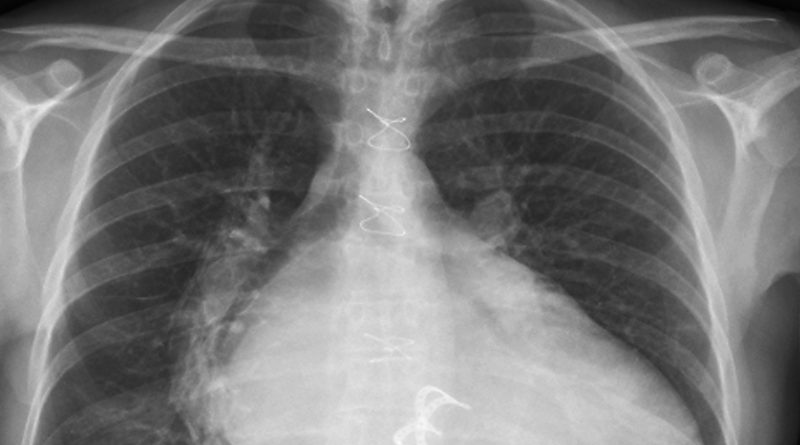

La Justicia falló a favor de un ciudadano de la provincia de La Pampa que demandó a una compañía de seguros por mala praxis. El hecho que desencadenó la denuncia fue una operación ante la sospecha de un tumor, el cual en realidad eran una gasas que salieron en las últimas radiografías. Estas fueron dejadas por médicos en su interior durante una cirugía de válvula del corazón.

El objeto en su interior, de más de 30 centímetros, fue suficiente para que la Cámara de Apelaciones Civil, Comercial, Laboral y de Minería de Santa Rosa fallara a su favor. De esta manera, admitió de manera parcial la demanda contra los cirujanos.

Hace más de dos años, el demandante debió ser sometido a una operación de válvula de corazón. Al detectarse el supuesto tumor, o quiste hidatídico, en otro establecimiento médico, tomaron la decisión de llevar a cabo una nueva cirugía. Sin embargo, al momento de llegar a la zona en cuestión, se toparon con, lo que la ley denominó, un “oblito olvidado”.